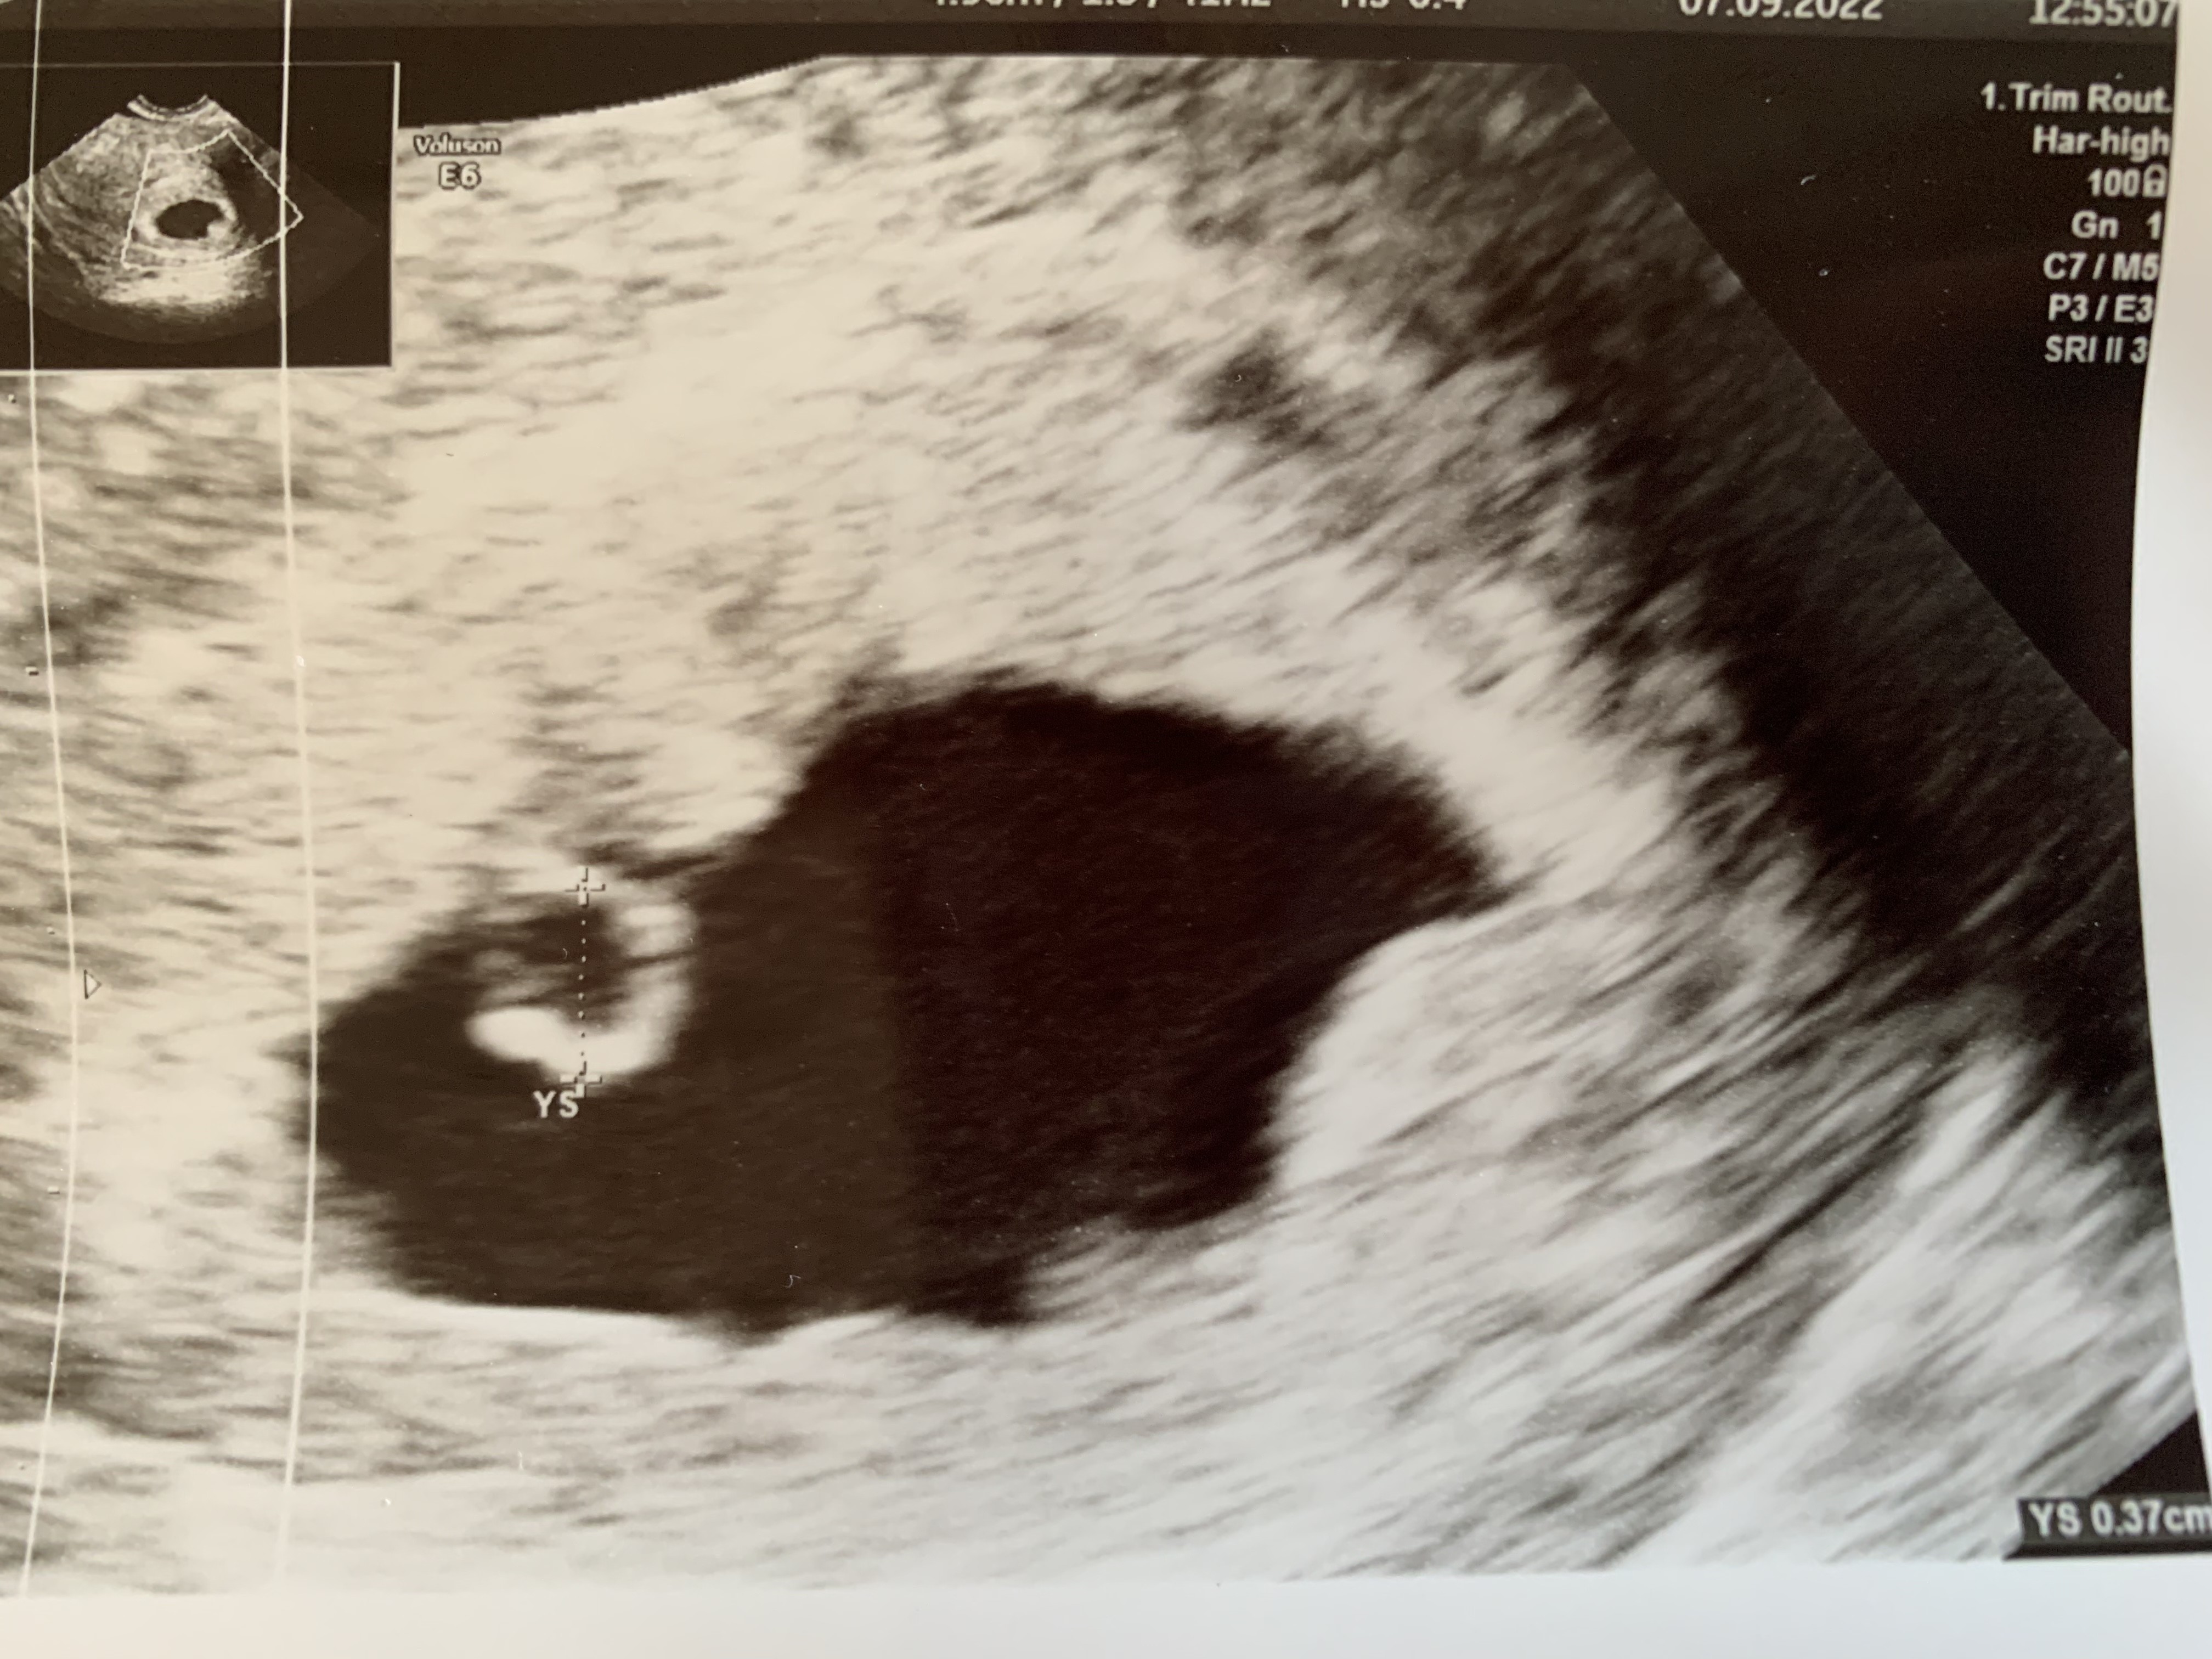

O widzisz ciałko żółte ma 0.37mm jak lekarz ma dobry sprzęt to jak będzie 0.7 milimetra można zobaczyć serce. Przeciętnie teraz 1mm na dzień rośnie

Tak myślałam żeby jutro zrobić bete, wiec jak się zbiorę i pojadę to dam znac jaki mam wynikA wiesz przy jakiej becie masz ten pęcherzyk żółtkowy?